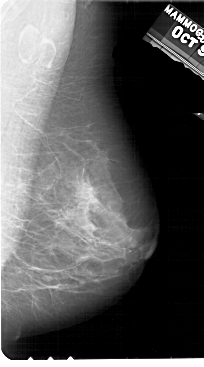

A_1945_1.LEFT_CC

LEFT_CC LINES 5491 PIXELS_PER_LINE 3271 BITS_PER_PIXEL 12 RESOLUTION 43.5 OVERLAY

FILE: A_1945_1.LEFT_CC.OVERLAY

TOTAL_ABNORMALITIES 1

ABNORMALITY 1

LESION_TYPE CALCIFICATION TYPE PLEOMORPHIC DISTRIBUTION CLUSTERED

ASSESSMENT 4

SUBTLETY 2

PATHOLOGY BENIGN

TOTAL_OUTLINES 1

BOUNDARY